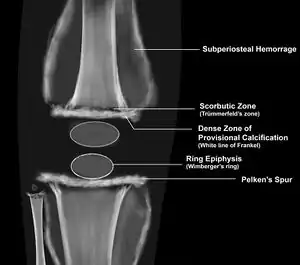

Wimberger's ring sign refers to a circular calcification surrounding the osteoporotic epiphyseal centers of ossification, which may result from bleeding.[1] It is seen in cases of scurvy.[1]